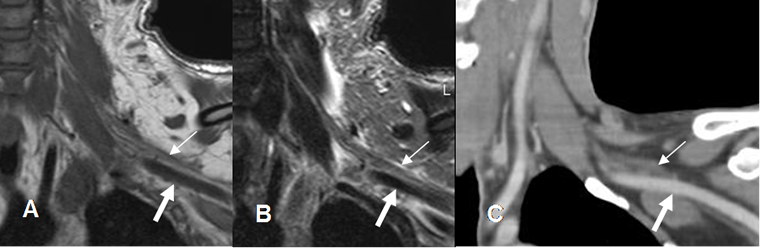

Fig 4. Raíces normales.

A: RM coronal en T1, B: RM coronal en T2 y C: TAC reconstrucción coronal. Raíces normales hipointensas, en la RM (Flechas delgadas), por encima de los vasos subclavios. (Flechas gruesas).